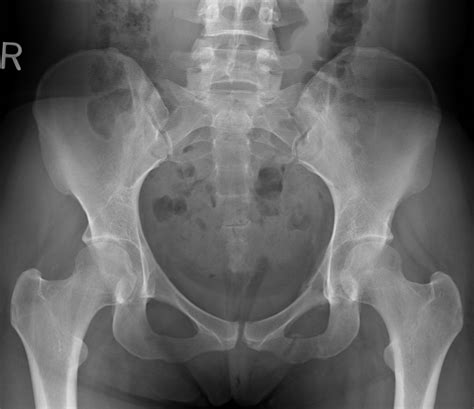

Normal Hip X Rays are a type of radiographic imaging used to visualize the hip joint and surrounding structures. This non-invasive procedure helps diagnose a wide range of conditions, including fractures, dislocations, arthritis, and developmental issues. The hip joint is a complex structure composed of the femoral head, acetabulum, and supporting ligaments and muscles. Normal Hip X Rays provide a clear view of these components, aiding in accurate diagnosis and treatment planning.

Interpreting Normal Hip X Rays requires a trained eye and a thorough understanding of hip anatomy. Radiologists look for specific features and measurements to determine the health of the hip joint. Key areas of focus include:

Common Findings in Normal Hip X Rays

Normal Hip X Rays can reveal a variety of conditions, ranging from minor injuries to severe degenerative diseases. Some of the most common findings include:

In addition to these conditions, Normal Hip X Rays can also detect other abnormalities, such as tumors, cysts, and congenital deformities. The images provide valuable information that guides further diagnostic tests and treatment plans.